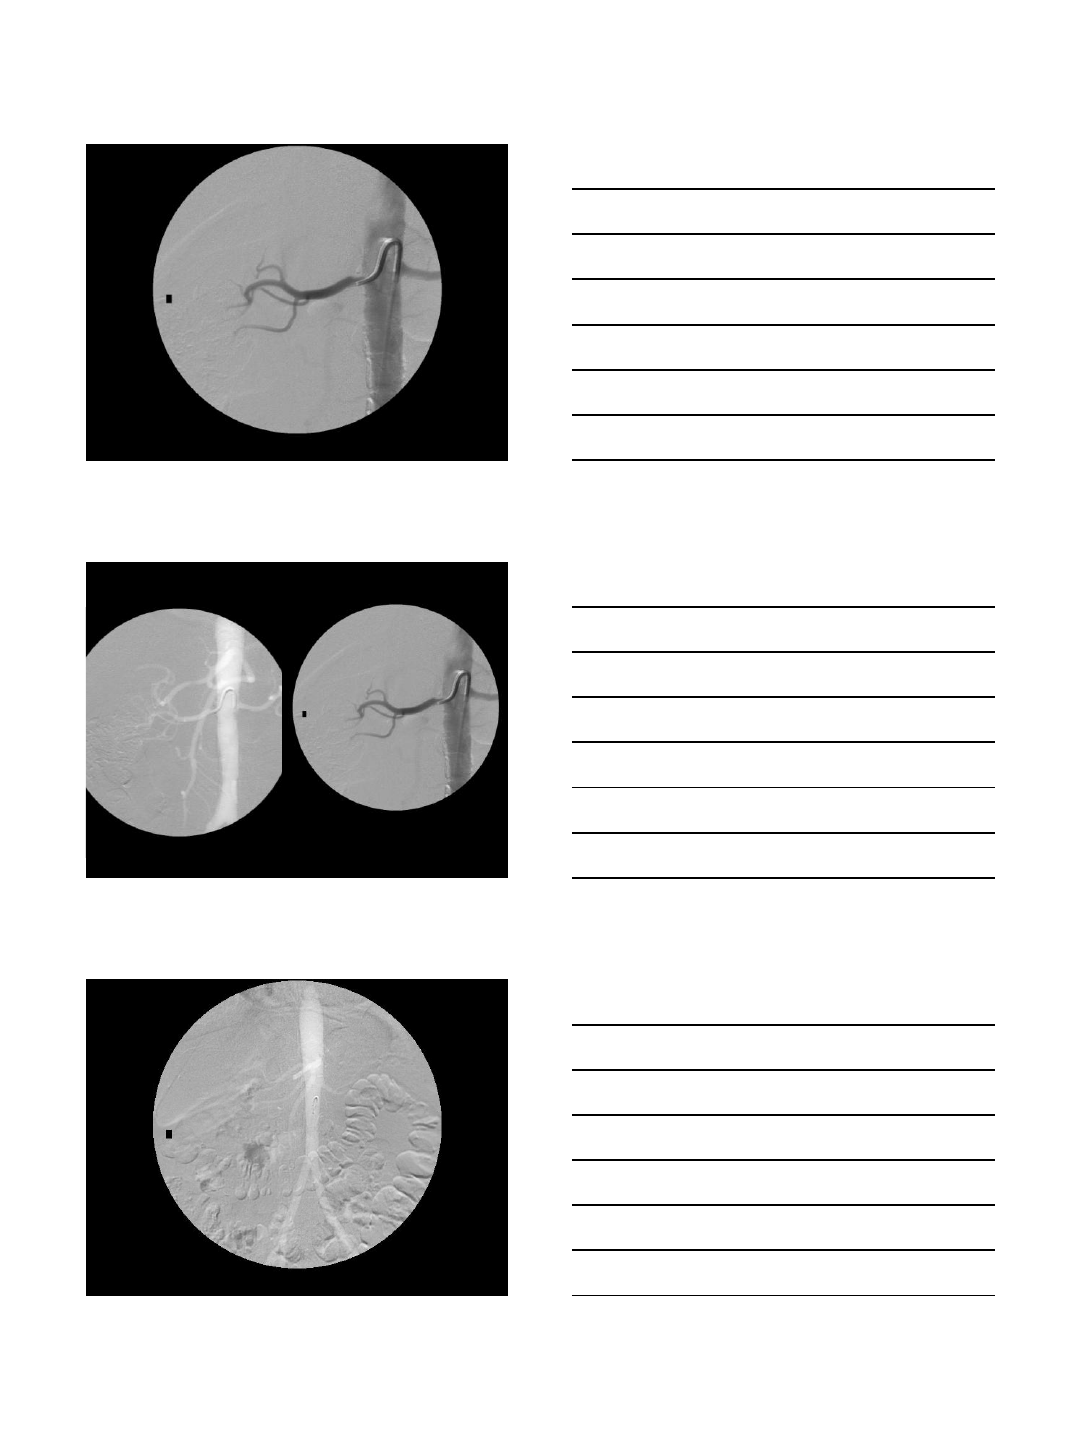

ANEURYSM REPAIR

Case Presentation

•78 year old man with severe atherosclerotic

disease, chronic renal failure with a stable

serum creatinine at 2.5 mg/dL and a large

iliac artery aneurysm

•Needs aneurysm repair but it is desirable to

CO2 arteriogram and embolization

•Iliac aneurysm coiling with CO2

•AAA stent-graft using CO2 & IVUS

•Total contrast used: 30 cc

•Renal function unchanged